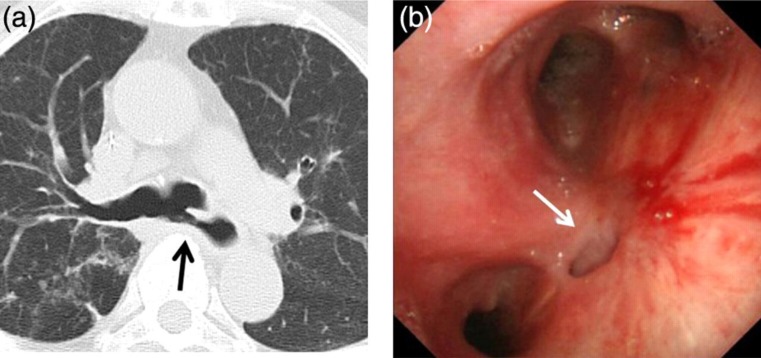

虽然手术是获得性良性气管食管瘘的常用治疗策略,但有时这种方法是禁忌的或患者拒绝手术治疗。在此报告中,我们描述了一例因支气管动脉输注化疗而在隆突水平发生气管食管瘘的患者。多种治疗策略,包括气道支架置入术、食管支架置入术、微线圈闭塞术或氰基丙烯酸酯胶,均不能实现闭合。我们随后通过改良的硅支架和金属支架的组合实现了瘘的闭合。

Although surgery is the usual management strategy for acquired benign tracheoesophageal fistula, sometimes this approach is contraindicated or the patient declines surgical management. In this report, we describe a case of a patient with tracheoesophageal fistula at the level of the carina due to bronchial arterial infusion chemotherapy. Closure could not be achieved in response to multiple treatment strategies, including airway stenting, esophageal stenting, occlusion with microcoils, or cyanoacrylate glue. We subsequently achieved closure of this fistula through the combination of a modified silicon stent and metallic stents.